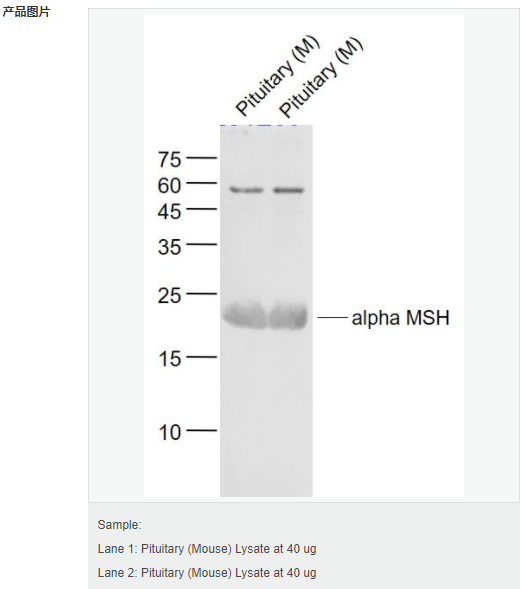

交叉反應:Mouse(predicted:Human,Rat,Rabbit) 推薦應用:WB,IHC-P,ELISA

交叉反應:Mouse(predicted:Human,Rat,Rabbit) 推薦應用:WB,IHC-P,ELISA

交叉反應:Mouse(predicted:Human,Rat,Rabbit) 推薦應用:WB,IHC-P,ELISA

| 產(chǎn)品應用 | WB=1:500-2000 ELISA=1:5000-10000 IHC-P=1:100-500 (石蠟切片需做抗原修復) not yet tested in other applications. optimal dilutions/concentrations should be determined by the end user. |

| 分 子 量 | 1.4kDa |

| 產(chǎn)品介紹 | This gene encodes a polypeptide hormone precursor that undergoes extensive, tissue-specific, post-translational processing via cleavage by subtilisin-like enzymes known as prohormone convertases. There are eight potential cleavage sites within the polypeptide precursor and, depending on tissue type and the available convertases, processing may yield as many as ten biologically active peptides involved in diverse cellular functions. The encoded protein is synthesized mainly in corticotroph cells of the anterior pituitary where four cleavage sites are used; adrenocorticotrophin, essential for normal steroidogenesis and the maintenance of normal adrenal weight, and lipotropin beta are the major end products. In other tissues, including the hypothalamus, placenta, and epithelium, all cleavage sites may be used, giving rise to peptides with roles in pain and energy homeostasis, melanocyte stimulation, and immune modulation. These include several distinct melanotropins, lipotropins, and endorphins that are contained within the adrenocorticotrophin and beta-lipotropin peptides. Mutations in this gene have been associated with early onset obesity, adrenal insufficiency, and red hair pigmentation. Alternatively spliced transcript variants encoding the same protein have been described. [provided by RefSeq, Jul 2008]. Function: ACTH stimulates the adrenal glands to release cortisol. MSH (melanocyte-stimulating hormone) increases thepigmentation of skin by increasing melanin production in melanocytes. Beta-endorphin and Met-enkephalin are endogenous opiates. Subcellular Location: Secreted. Tissue Specificity: ACTH and MSH are produced by the pituitary gland. Similarity: Belongs to the POMC family. SWISS: P01189 Gene ID: 5443 Database links: Entrez Gene: 5443 Human Entrez Gene: 18976 Mouse Omim: 176830 Human SwissProt: P01189 Human SwissProt: P01193 Mouse Unigene: 1897 Human Unigene: 277996 Mouse Unigene: 108195 Rat Important Note: This product as supplied is intended for research use only, not for use in human, therapeutic or diagnostic applications. |